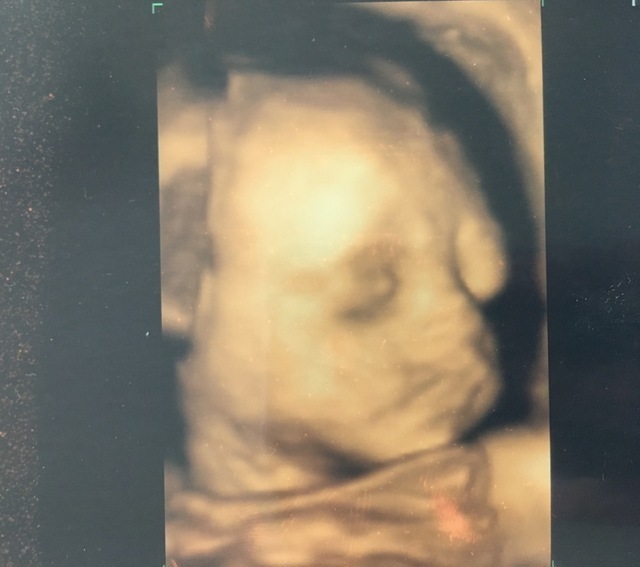

27週4日(27w4d・男の子)|rearea0404 さん(35歳)

私にとっても似ていて、おなかにいるのにリアルにうつってるので、母と最近の技術者は凄いなぁと話してました。生まれてきた赤ちゃんとほぼ同じでした。鼻はとてもリアルに似ていました。手の位置など生まれてからも、寝るときはその位置に置いて寝るので本当に凄いです。